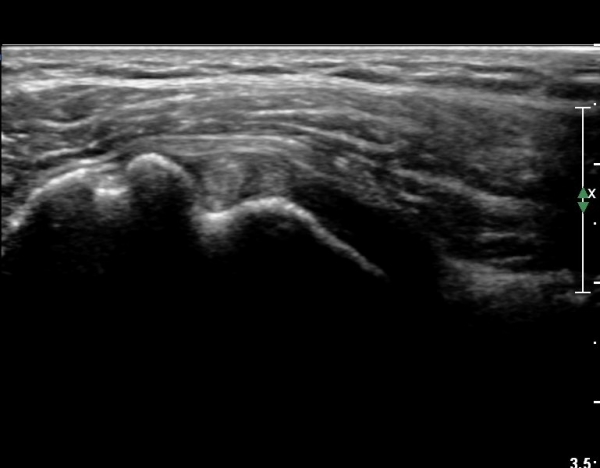

ŽÃËÀÚ¸¦ Á¶±Ý ¾Æ·¡·Î À̵¿ÇÏ¿© À̵ιڱٰÇÀÇ È¾´Ü¸é°Ë»ç¿¡¼­ ÀÌµÎ¹Ú±Ù°Ç ÁÖÀ§ ¼ö¾×Àú·ù°¡ °üÂûµÈ´Ù(»çÁø 3, 4).

À̴ Ȱ¾×¸·¿°Áõ ¼Ò°ßÀ¸·Î Ãæµ¹ÁõÈıº ¶Ç´Â ȸÀü±Ù°³ ÆÄ¿­ ½Ã ÈçÈ÷ °üÂûµÇ´Â

¼Ò°ßÀÌ´Ù.